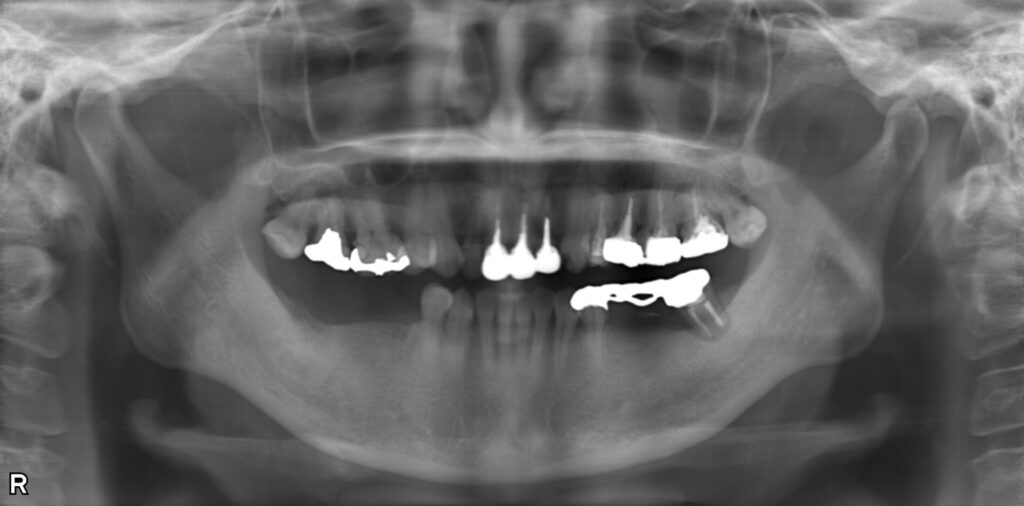

症例写真

(右下の奥歯にはインプラントが適切な角度で埋入されている)

口腔内の状況

骨が薄い部分があったため、6ヶ月間骨とインプラントの結合をまつ

⑦インプラントの上部構造と上の前歯にCAD/CAMによる白い歯を装着